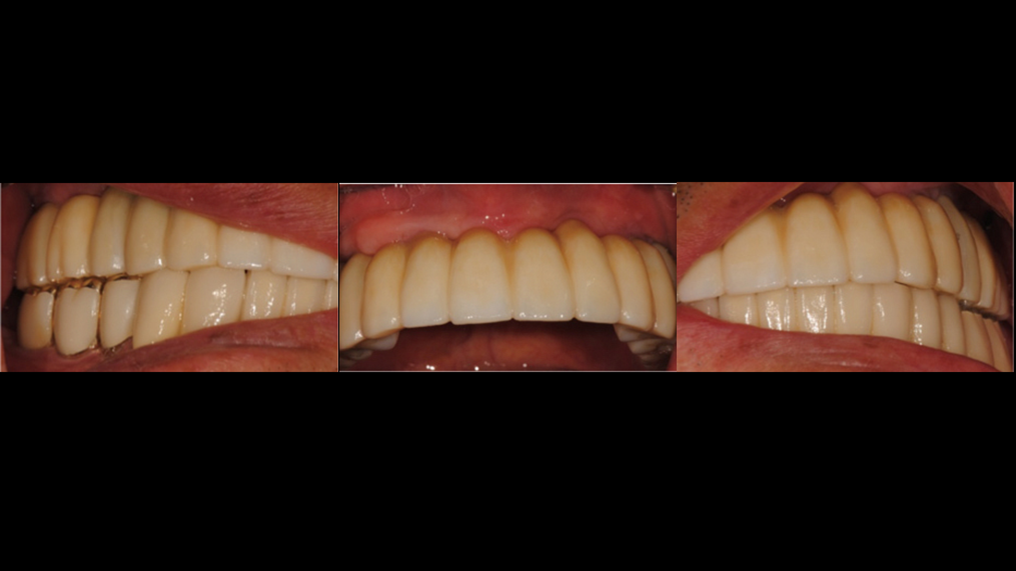

“AnyRidge shows excellent esthetic results

with Zirconia prosthesis in full-mouth rehabilitation case . ”

Clinical case: AFull transition from natural teeth to all-on-6 bridges

with AnyRidge implants

- Courtesy of Dr. Rabih Abi Nader, UAE -

Keywords

Full-mouth rehabilitation, minimal layering, Zirconia, all-on-6, life changing result, edentulous ,Dr. Rabih Abi Nader, AnyRidge

Products:

AnyRidge implant system